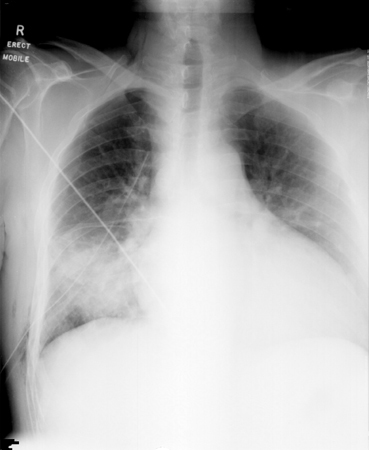

[Figure caption and citation for the preceding image starts]: Cryptococcus neoformans-ით გამოწვეული კვანძები ფილტვში, ქვედა მარჯვენა და ქვედა მარცხენა წილებში.რადიოლოგიის დეპარტამენტის კოლექციიდან, The Prince Charles Hospital, Chermside, Brisbane, Australia; გამოიყენება ნებართვით [Citation ends].